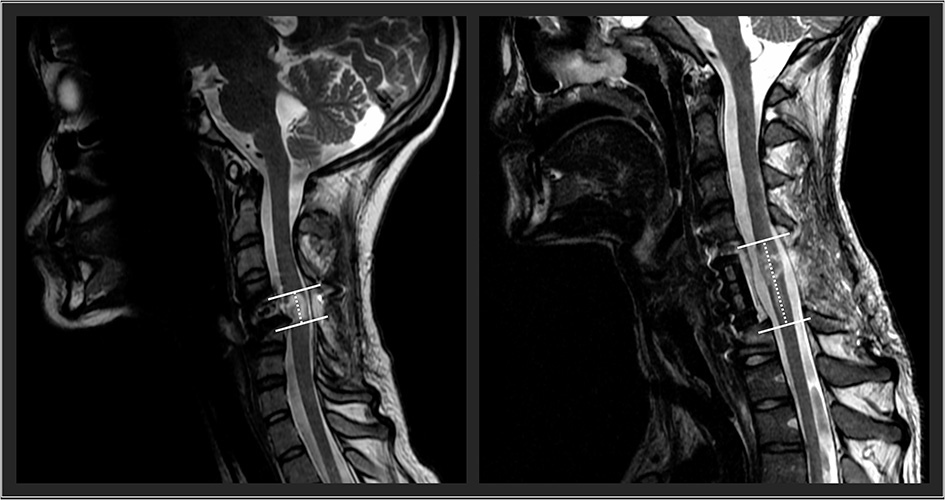

Future research should examine the influence of spinal cord lesion characteristics on the responsiveness to TSCS. In an exploratory approach, using our participants' available clinical sagittal T2-weighted magnetic resonance imaging, we found that spinal cord lesion length was negatively correlated with participants' outcomes. High correlations were found with UE motor change scores (rs = −0.64), LE motor change scores (rs = −0.85), and the nine-hole peg test (rs = −0.77). With further research and refinement, lesion length (Figure 2) could be used to identify optimal responders and stratify participant groups for prospective investigation of TSCS. The hope is that with an increased participant sample size using high resolution MRI in a prospective investigation, future research could investigate how lesion length and other measures of spinal cord damage such as widths of midsagittal tissue bridges (29–34), lesion volumes (35), atlas-based estimates of tract damage (36–38) relate to responsiveness to spinal cord stimulation. This work is underway.

Figure 2

Two representative participants' midsagittal T2 weighted MRIs are shown. The cranial-caudal lesion boundaries are identified in white lines, while the lesion lengths are depicted in the dotted lines. On the left panel, this participant had a relatively shorter lesion length compared to the participant's lesion in the right panel.